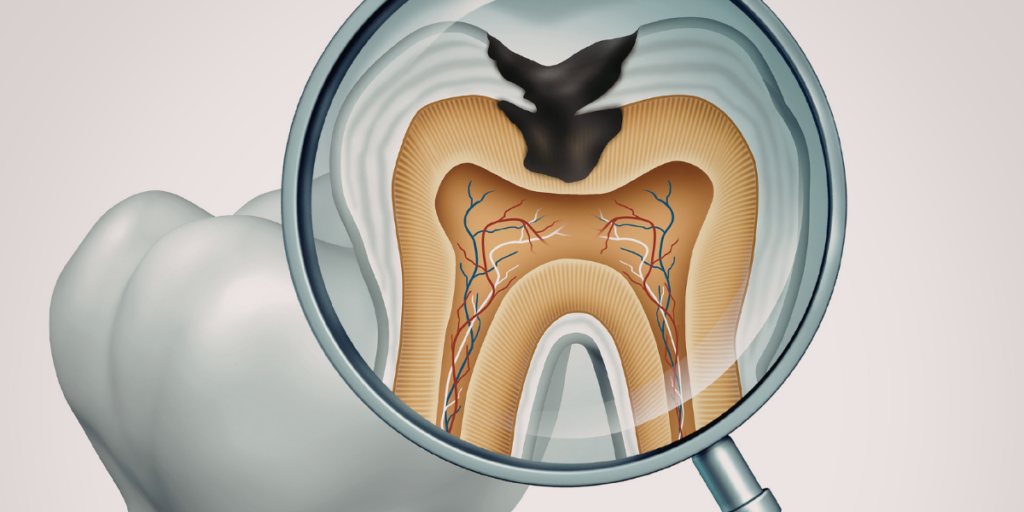

Cavities start when bacteria in your mouth make acid. That acid can wear down enamel over time. Some people get cavities despite good oral hygiene because a few hidden factors push the mouth toward decay. Dry mouth, frequent snacking, and deep grooves in teeth are common causes of cavities.

Deep Grooves And Pits That Trap Bacteria

Deep grooves in molars can trap plaque where toothbrush bristles can’t reach. That can lead to repeat cavities in the same back teeth, even with careful brushing.

If you keep getting cavities in your molars despite good oral hygiene, tooth shape may be a big reason. Sealants can help block those grooves and protect the tooth surface.